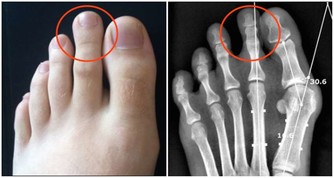

胃食管反流病算得上是消化科最常見的疾病,門診上來了個病人,問問有哪裡覺得不舒服,很多人都會回答,總覺得從胃裡往上反酸水,或者心口窩那裡總是燒的厲害,這樣描述症狀的病人十有八九都是出現了胃食管反流病。

胃食管反流病是怎樣來的?原因其實很簡單,我們的食管和胃相連的地方叫做賁門,你可以把它想像成一個開關,當食物進入的時候,它開放讓食物進入胃內,然後參與整個的消化過程,當沒有食物進入的時候,它會閉合,防止胃酸進入食管。

但是在某些病理條件下,這個閥門變得不好使了,胃液反復多次通過這個開關進入食管,時間一長,食道黏膜受損,病人就會出現燒心的症狀。